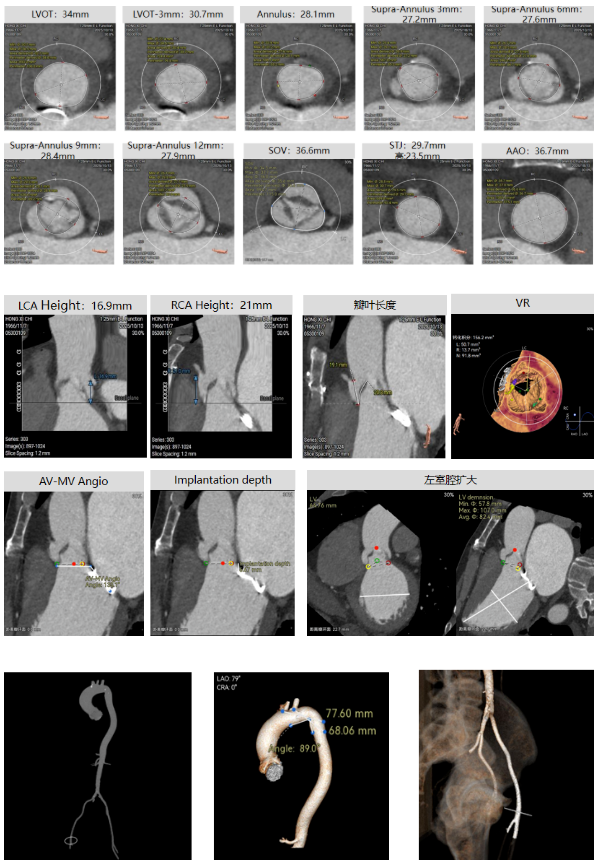

初冬的塞上大地,贺兰山脉覆着薄霜,黄河之水仍漾着温润波光,苍茫辽阔的西北风光里,藏着独有的坚韧与温情。这片孕育了西夏文化、承载着丝路底蕴的热土,自古便有着守望相助的人文情怀,而守护生命安康,更是这里医者们从未动摇的使命。在这片土地的医疗高地宁夏医科大学总医院,由刘旭东教授、李晓东教授、张玉京教授组成的心脏瓣膜专家团队,近日以一场高难度的创新手术,为心血管疾病患者点亮了新生希望 —— 成功完成全球首款预装干瓣 ProStyle A® 的全国首批临床植入。 此次手术的患者病情特殊,不仅主动脉瓣中度狭窄合并中 - 重度关闭不全、瓣叶增厚,还曾接受二尖瓣位机械瓣植入术,瓣膜锚定难度极大。团队历经多轮严谨评估,最终敲定采用 ProStyle A® 介入治疗方案,凭借精湛医术与周密预案精准完成瓣膜释放。这场手术的成功,标志着医院在结构性心脏病介入治疗领域迈入全生命周期管理新阶段,也成为国产创新器械与临床智慧深度融合的重要里程碑。 刘旭东教授 宁夏医科大学总医院 传统戊二醛保存的瓣膜,长期使用中易因组织钙化、柔韧性下降导致功能衰减。但 ProStyle A® 的优势在于两点:一是金仕生物的专利抗钙化技术,通过纳米级工艺去除组织内细胞碎片与磷脂,同时封闭游离醛基 —— 这相当于从源头阻断了引发瓣膜钙化的‘关键诱因’;二是干式存储技术,最大程度保留了心包组织原有的亲水亲油平衡,让瓣叶始终维持天然的曲柔性,确保长期开合功能稳定。对像此次手术这样的心功能受损患者来说,这种‘抗钙化 + 保柔韧’的双重设计,意味着瓣膜能更长时间地维持正常功能,减少二次干预的风险,真正实现‘一次植入,长期获益’,这正是全生命周期管理理念在器械选择上的核心体现。” 患者病史 主诉:反复胸闷气短2月余 术前超声提示:二尖搬位机械置换术后,功能未见明显异常,瓣周返流(轻-中度) 主动脉瓣狭窄(中度)并关闭不全(中-重度)VP:3.3mm/s,PG:45mmHg 三尖瓣返流(轻度) 左房显著增大左室明显增大主肺动脉增宽 左室收缩功能明显减低 术前CT 三叶瓣,瓣叶增厚轻度钙化,主动脉根部直径27.8mm,LVOT直径34.7mm。 双侧冠脉开口高度尚可,左右冠切线角度测量右冠瓣叶长于冠脉开口上缘到根部距离,瓦氏窦偏大。 左室腔扩大,EF较低,有一定循环崩溃风险,主动脉瓣环水平夹角52.7度,非横位心患者,主动脉弓宽度、角度可;二尖瓣机械瓣(横列式)置换术后AV-MV夹角130度,距离主动脉瓣虚拟瓣环6.67mm。 外周走行尚可,全主动脉基本无钙化,右股低分叉,血管内径可,血管内壁存在纤维增厚。右侧为主入路能够支持20F大鞘通过。 手术策略 右侧股动脉为主入路,预装ProStyle A® AV32主动脉瓣膜,使用20F大鞘,不预扩,建议最终理想释放位置0-瓣下2mm。 手术过程 在右股动脉穿刺建立通路后,将右冠送入冠脉保护,后顺利送入大鞘,经食道超声及血管造影确认路径稳定,将ProStyle A® AV32号瓣膜精准释放于目标位置(瓣下2mm),超声显示无瓣周漏,平均跨瓣压差4mmHg,心功能明显改善,患者生命体征平稳。 右冠保护 同时主动脉根部造影 定位 缓慢释放瓣膜 最终造影,位置形态良好,冠脉充盈良好 术后超声:显示瓣膜呈现较好的圆形,最大流速133cm/s,平均跨瓣压差显著降低至4mmHg,瓣周无反流。 ProStyle A®预装干瓣——助力临床最优化解决方案: 平衡径向支撑力:ProStyle A®瓣架网孔比例按照病例解剖结构的特殊设计,使瓣膜在狭窄最重的地方良好的撑开, 同时避免对瓣环及周边组织的过度压迫,有效降低传导阻滞风险。 精准释放:底部桶状设计更易迅速锚定,协同释放张力小,助力最终精准释放; 80%可回收设计:对于复杂解剖结构的患者,提供更充分的调整窗口,显著提升释放安全性与精准度并且80%可回收设计在释放过程中给予术者充分的容错空间。 预装干瓣 便捷顺安:金仕生物专利抗钙化技术运用纳米技术去除组织内的细胞碎片和磷脂,封闭游离醛基,从根本上阻断了瓣膜钙化的多项因素,显著提升了瓣膜的耐久性;同时,相比较传统戊二醛保存方式,干式存储最大限度的保留心包的亲水亲油平衡,还原组织天然曲柔性,进一步保障了瓣叶开合,保证长期耐久性。 专家简介 刘旭东 宁夏医科大学总医院(点击查看专家详细简历) 李晓东 宁夏医科大学总医院(点击查看专家详细简历) 张玉京 宁夏医科大学总医院(点击查看专家详细简历) · END ·